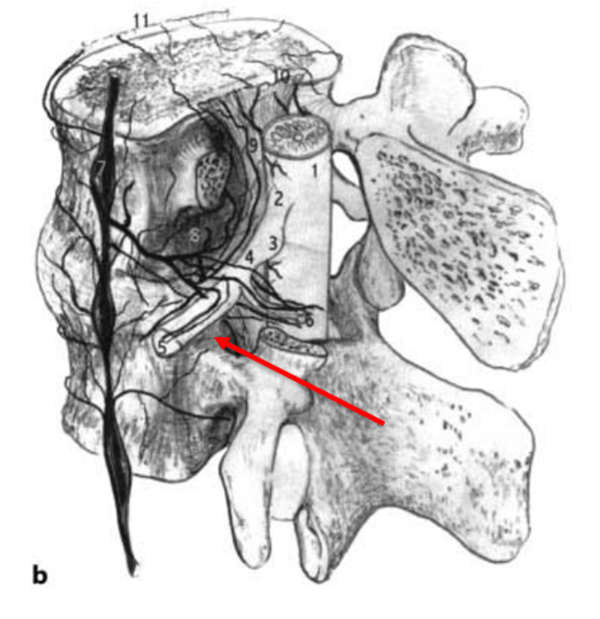

无论是RN入路还是SP入路,两种注射方法均是把药物注射至神经根的背侧或侧方,而通过对神经解剖学的认知,人们认识到,为了缓解神经疼痛,需要把药物注射至腹侧硬膜外间隙,即椎间盘/硬膜交界处、椎弓根的内侧,使得药物覆盖神经根,才能更为有效。所以,最理想的方案应该是把穿刺针通过穿刺置于椎间盘的背侧,硬膜囊的腹侧。通过解剖学发现,尽管脊柱通过骨性结构及韧带结构把重要的脊髓神经保护其中,形成一个相对封闭的结构,但仍保留了与椎管相同的孔道,正像圣经中所言:“when God closes this door, he will open another door for you”,而这扇窗,就是椎间孔。

其实早在1973年,Parviz kambin教授就提出了kambin三角,kambin三角较Bogduk三角拥有更大的空间结构,能有效避开重要的神经和血管。因此,利用Kambin三角进行穿刺,将穿刺针尖置于病变间隙硬膜囊腹侧,同时具备了安全和有效的特点。Jasper JF于2007年介绍了这种方法,他将这种方法称之为Retro-discal approach(RD)入路。Jasper认为,一个最佳的注射位置应该是使得药物覆盖椎间盘病变区、椎间盘神经界面和受刺激的节段性神经。这种穿刺方法同时也是经皮椎间孔镜置入工作通道的路径,更为外科医生所熟悉,也使得“经椎间孔注射术”名副其实。该方法成为了脊柱外科医生、疼痛科医生和神经外科医生最为推崇和认可的穿刺方式。在2014年,NASS把经椎间孔注射术写入了《腰椎间盘突出症诊疗指南》中,推荐等级为A级。

图7